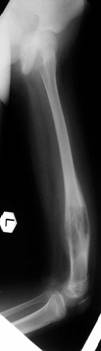

Pre Op

>X-ray (Left femur)

osteolytic lesion

• (?) osteosarcoma